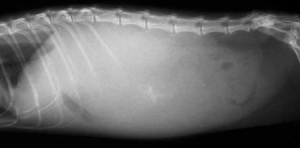

腹水究竟是什么?腹水指腹腔内蓄积非生理性液体 水和淋巴液,也称为腹腔积液,属于一种继发性疾病。

幼年犬和老年犬容易出现,菜叶说说,典型的表现为腹围增大、腰背凹陷。

腹水如何做诊断?腹水的诊断并不难,难点在原发病因的寻找,往往都需要大量的检查,这意味着检查费用会比较高。

比较有价值且性价比较高的检查包括:血常规、生化、尿检、X光片、超声 腹超、心超、胰腺炎检测等,其他检查可以根据具体情况进行选择 腹水液体成分评估、胆汁酸检测、活检等。